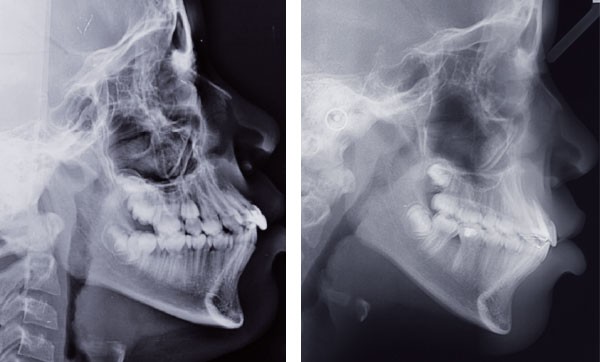

Orlhane B., 10 ans, est adressée à l’unité fonctionnelle d’orthodontie de l’hôpital Bretonneau par son dentiste suite à un traumatisme sur la 11. Le trait de fracture est infra-osseux et ne permet pas la réalisation d’une restauration prothétique de cette dent. Le praticien nous demande de réaliser une extrusion orthodontique afin d’égresser la dent sans que son parodonte suive le mouvement dentaire et d’augmenter ainsi l’espace biologique. La longueur radiculaire permet ce mouvement (rapport couronne/racine postextrusion inférieur à 1) et un traitement à l’hydroxyde de calcium est réalisé transitoirement durant le déplacement orthodontique. L’obturation finale sera réalisée une fois que les limites du trait de fracture seront supra gingivales et permettront la mise en place d’un champ opératoire étanche.

À l’examen clinique, Orlhane présente une classe I biproalvéolie aggravée par 11 fracturée et 25 enclavée et une classe II canine légère gauche. Cette malocclusion est associée à une classe II squelettique par promaxillie sur un schéma facial hyperdivergent. Il est décidé de ne pas traiter la biproalvéolie et la classe II squelettique modérées d’origine ethnique chez cette patiente.